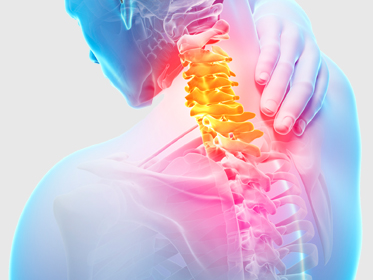

�㸮��ũ, ���༺��ũ, ��ũ������, ô���� �� ����, ô�߰�������, ô������������ ��

��Ծ��� ô�� �� ������ ������ �а� ��� ���� ������ �ٷ���� ������ ���߾� ô�߿� ô�� �ֺ������� ����� �����ϰ� �����ϴ� �������Դϴ�.

�߳���� ġ�� ����

ô�߿� ������ ������ �ٸ��� �����ν� ������ ġ���ϴ� ���� �������� �մϴ�. ��ü�� �¿� �뷱���� �������ν� ����� ������Ѽ� ������ȯ�� ��Ȱ�ϰ� �ϴ� ġ����Դϴ�.

�߳���� ġ�� ȿ��